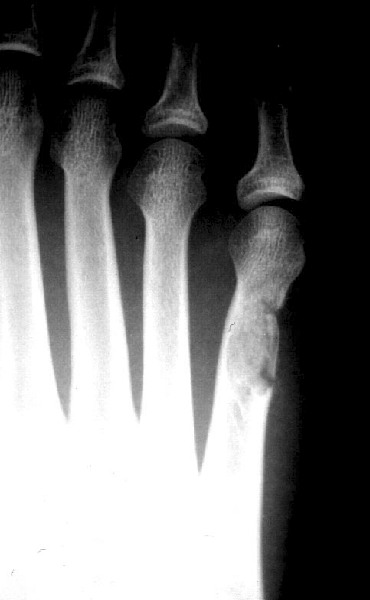

There are many instances when it is appropriate for the foot and ankle surgeon to use bone grafts in order to enhance a patient’s clinical outcome. When it comes to reconstructive osteotomies for angular realignment, arthrodeses and the repair of nonunions and cystic bone lesions, these are often best performed with procedures that take advantage of the many desirable features of bone grafts and, more recently, bone graft substitutes. Before discussing the details of bone graft substitutes, it is helpful to review the bone graft options that are available to the surgeon. These options include: cancellous and/or cortical bone, allogeneic (typically freeze-dried) cadaver bone and autogenous bone. Cancellous bone offers a porous, osteoconductive environment and ease of incorporation. However, it conveys limited structural strength and ability to retain fixation devices. Cortical bone, on the other hand, offers tremendous structural integrity, but it is slow to incorporate in comparison to cancellous bone. Allogenic bone implants offer ease of use, ready availability and provide a wide range of configurations that include cortical and cancellous bone in various proportions. However, despite rigorous measures related to the procurement and preparation of allogeneic tissue products, there remains a very small but real risk of disease transmission and hypersensitivity reaction.1,2 The autogenous corticocancellous bone graft, which is typically harvested from the iliac crest, remains the gold standard for comparison of all other grafting materials. In reconstructive foot and ankle surgery, the calcaneus offers a reliable source of autogenous bone graft material. Unfortunately, however, autogenous sources of corticocancellous bone are limited and there is distinct morbidity associated with harvesting autogenous bone. Banwart et al., performed a meta-analysis of the related literature and observed that use of autogenous iliac crest bone grafts was associated with a 25 to 45 percent complication rate. They also noted that 40 percent of patients related harvest site pain up to five years postoperatively.3 For these reasons, the emergence of bone graft substitutes for enhancement or augmentation of bone grafting procedures, as well as the techniques of bone callus distraction, have proven to be of great service in recent years.